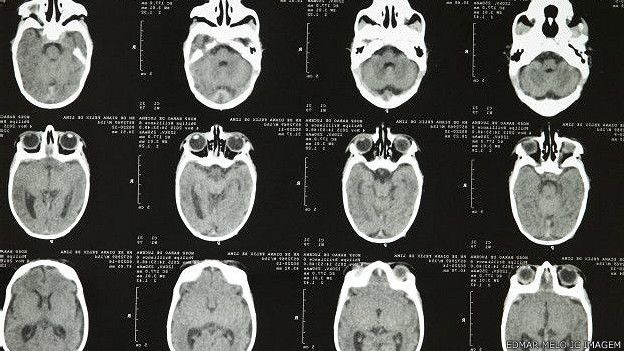

Literalmente, quiere decir “cabeza pequeña”, es decir, mucho más pequeña que lo normal para un bebé de ese tamaño y género. Suele indicar que hubo un crecimiento cerebral atrofiado durante el embarazo. A veces ocurre después del nacimiento, cuando el cerebro o el cráneo no crecen normalmente, una de las razones por las que el médico mide la circunferencia de la cabeza cada vez que una madre lleva a un bebé al médico.